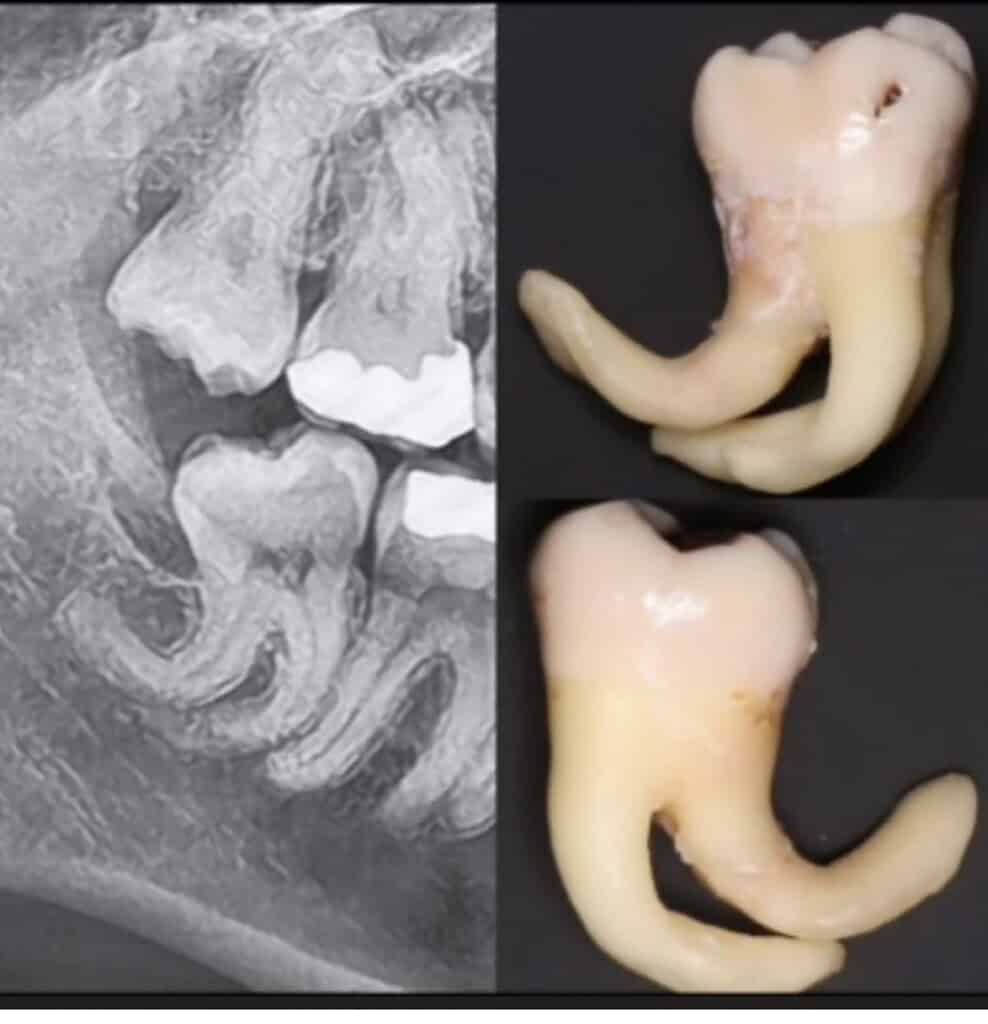

Ever wondered how we remove the most tricky teeth?

This is where Abs the Oral Surgeon comes in... he forges his own instruments so he can take out the most complicated teeth!